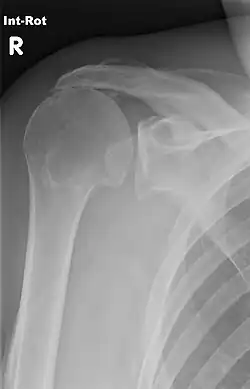

Röntgen

Nur selten kann man im einfachen Röntgenbild die verheerende Schädigung der Rotatorenmanschette so eindeutig erkennen (siehe Bild). Das hier gezeigte Impingement spricht für eine weitgehend vollständige Degeneration der Rotatorenmanschette, die Bursa subacromialis ist vollständig zerstört. Die Gelenkkonturen des Oberarmkopfes, aber auch die Röntgenstruktur der Gelenkpfanne zeigen bereits Merkmale einer fortschreitenden Arthrose.